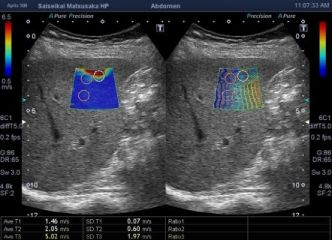

腹部超音波検査では、肝線維化を評価する超音波エラストグラフィ機能を搭載した装置を導入し、肝臓の硬さの程度を数値化して線維化を評価しています。 主に慢性肝疾患患者さんの経過観察や肝線維化進行程度の把握には超音波検査と血液検査における肝線維化マーカーであるM2BPGi、FIB4indexなどと併せて評価することで、総合的に判定することが可能です。超音波エラストグラフィは非侵襲的で簡便な検査のため健診領域においても腹部超音波検査のオプション項目として取り入れています。

超音波エラストグラフィ《臨床画像使用》